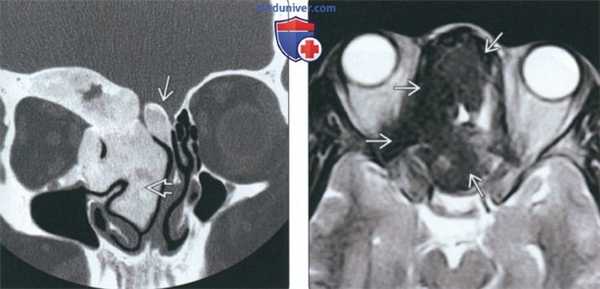

(Слева) При аксиальной «костной» КТ определяются классические признаки фиброзной дисплазии: выраженное вздутие левой верхнечелюстной пазухи с асимметричным выбуханием левой щеки, типичный вид «матового стекла». Обратите внимание на значительное уменьшение объема воздушной полости.

(Справа) При корональной костной КТ определяется фиброзная дисплазия с поражением правой нижней носовой раковины и латеральной стенки носа. Определяется выраженная экспансия раковины с изменениями в виде «матового стекла».

(Слева) При корональной «костной» КТ определяется экстенсивная фиброзная дисплазия орбит, петушиного гребня, решетчатой кости, среднего носового хода справа. Носовая перегородка отклонена влево.

(Справа) При аксиальной MPT Т2 в зоне фиброзной дисплазии определяется характерный выраженный гипоинтенсивный сигнал. Эти изменения типичны, когда наблюдаются совместно с «матовым стеклом» на КТ, и более диагностически значимы, чем гиперинтенсивные на Т2 очаги.

(Слева) На корональной КТ в костном окне определяется ПФД с поражением глазницы, петушиного гребня, решетчатого лабиринта, средней носовой раковины справа. Оцените типичную картину «матового стекла». Носовая перегородка смещена влево.

(Справа) На аксиальной МРТ (Т2ВИ) у этого же пациента определяется выраженный гипоинтенсивный сигнал в пораженных костях. Поражение однородное и сопоставимо с «матовым стеклом» на КТ. При большем количестве фиброзной ткани ожидаемы очаги с более интенсивным сигналом и более длительным временем повторения.